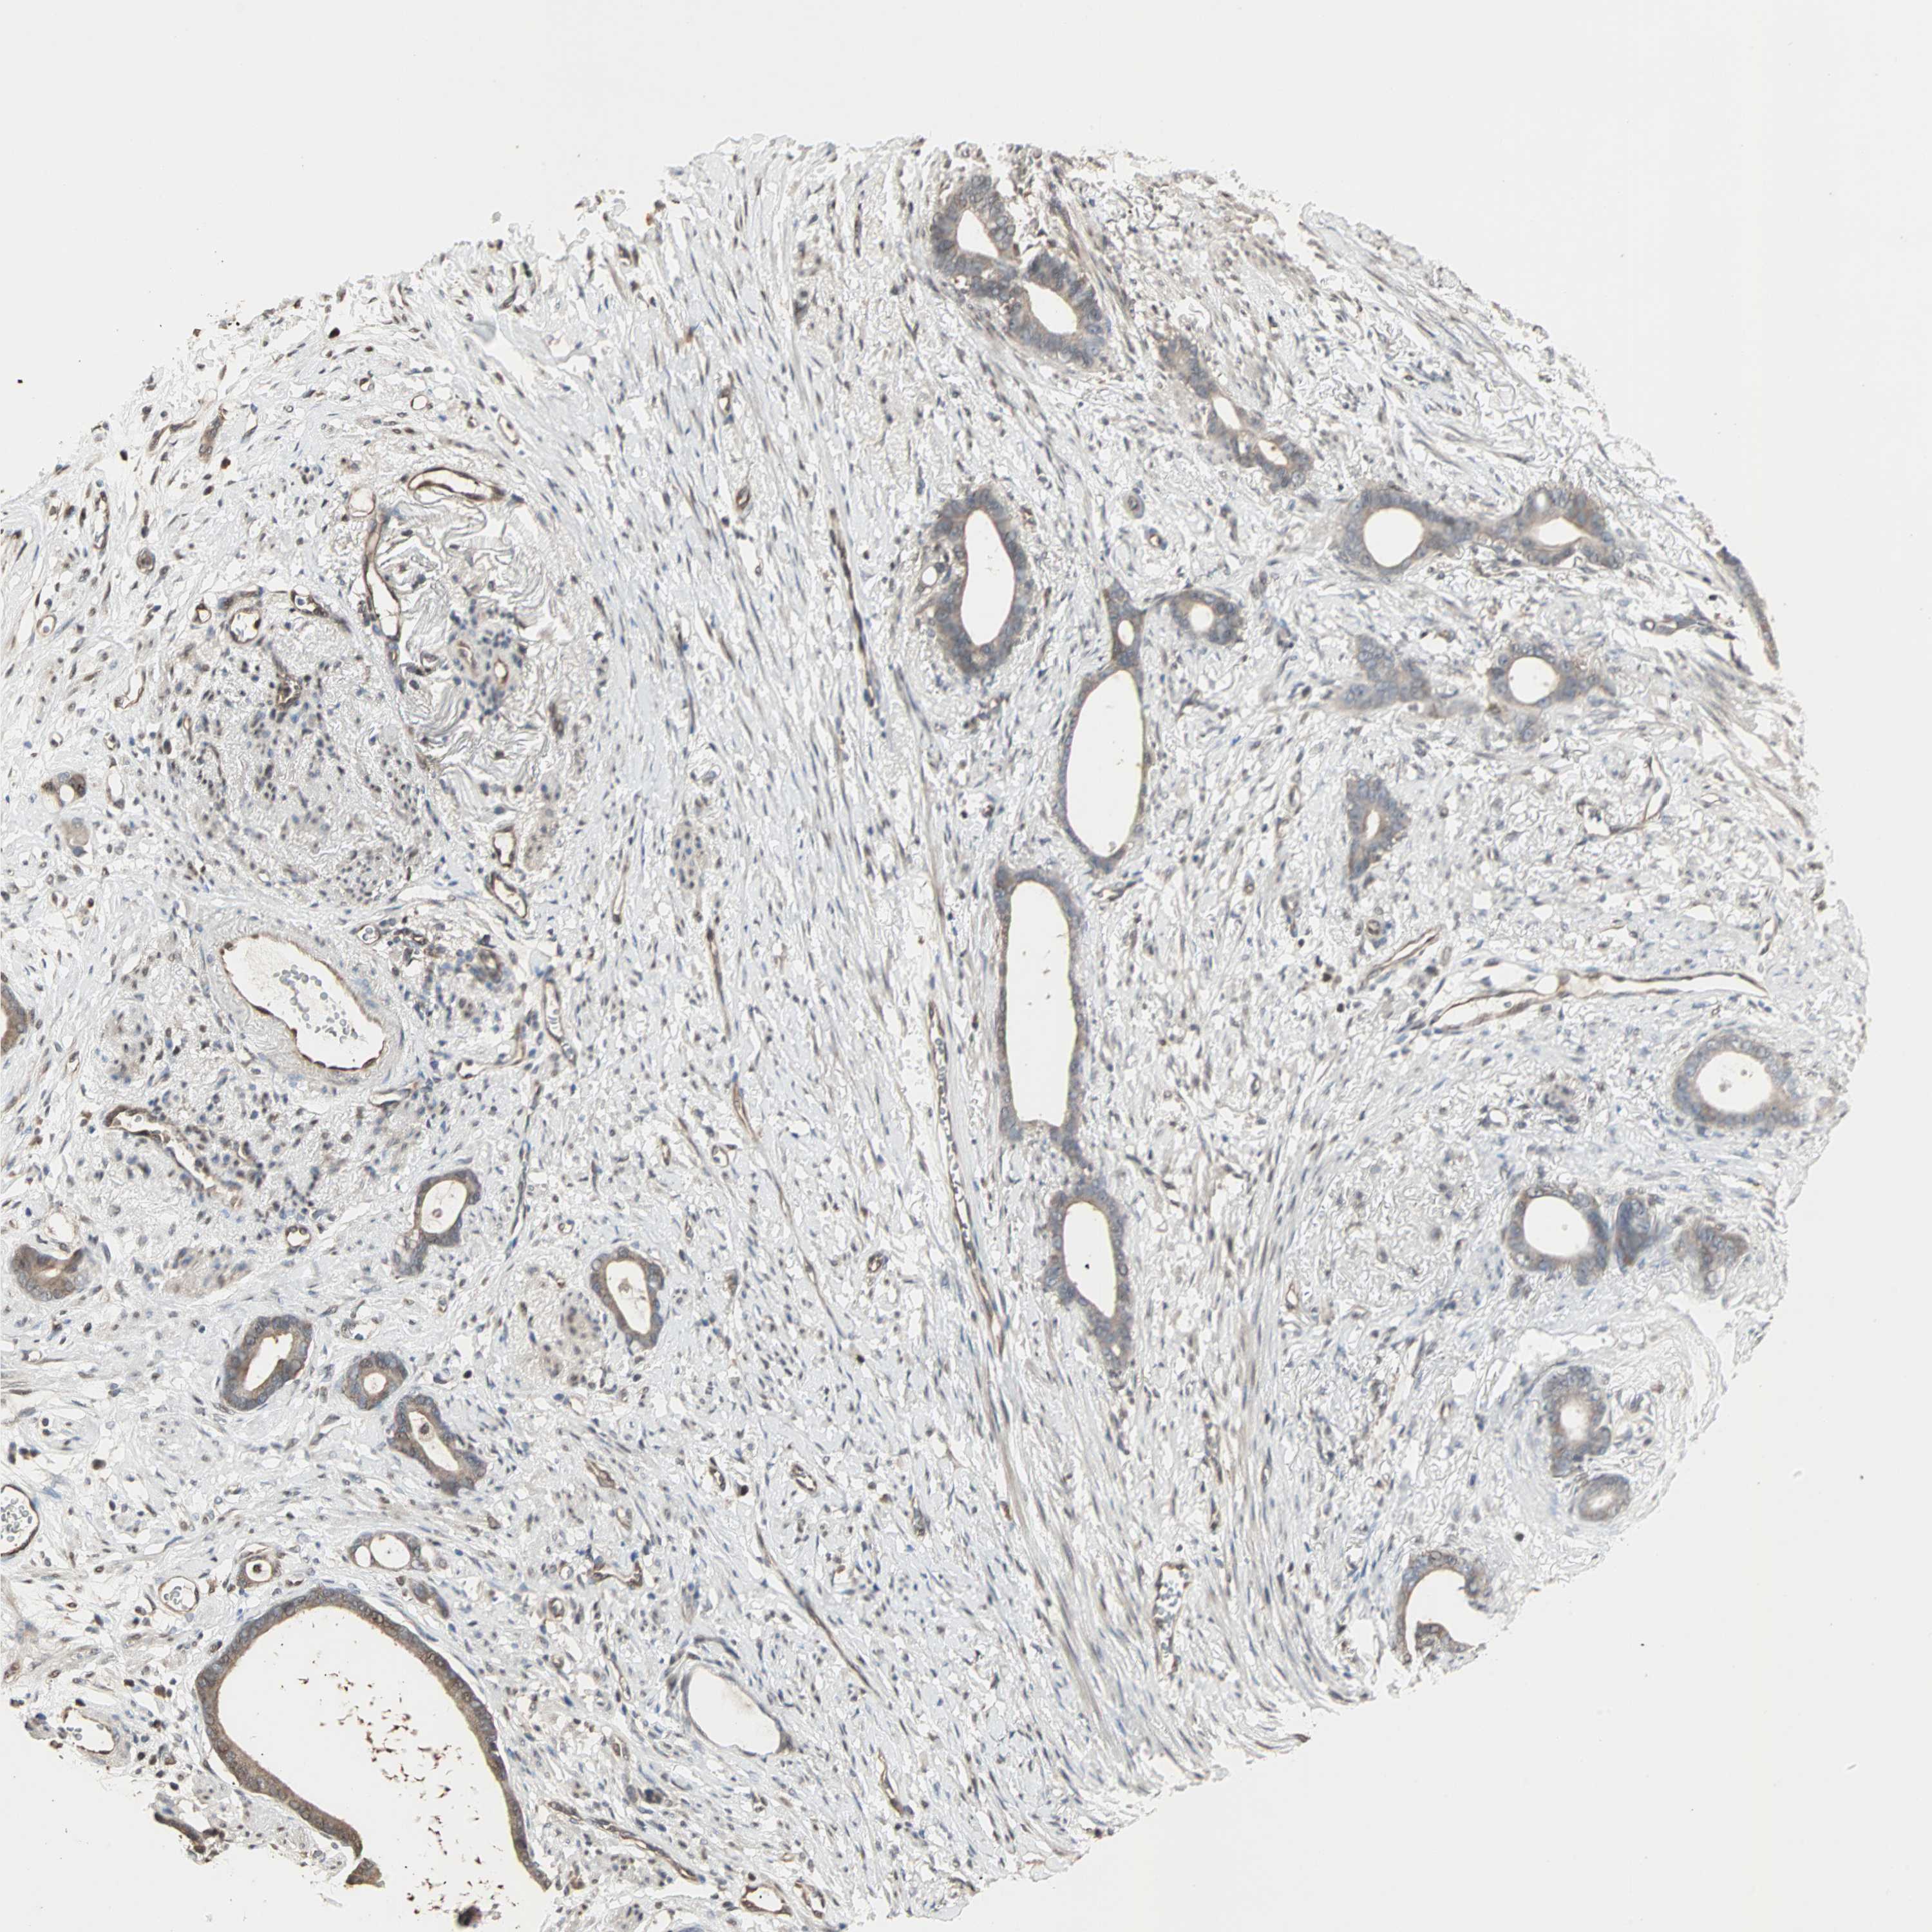

STOMACH CANCER - Protein expressioni

A mouse-over function shows sample information and annotation data. Click on an image to view it in a full screen mode. Samples can be filtered based on level of antibody staining by selecting one or several of the following categories: high, medium, low and not detected. The assay and annotation is described here.

Note that samples used for immunohistochemistry by the Human Protein Atlas do not correspond to samples in the TCGA dataset.

Antibody stainingi

Antibody staining in the annotated cell types in the current human tissue is reported as not detected, low, medium, or high, based on conventional immunohistochemistry profiling in selected tissues. This score is based on the combination of the staining intensity and fraction of stained cells.

Each image is clickable and will lead to virtual microscopy that enables deeper exploration of all samples and also displays staining intensity scores, fraction scores and subcellular localization as well as patient and tissue information for each sample.

Antibody HPA007716

Staining

High

Medium

Low

Not detected

Intensity

Strong

Moderate

Weak

Negative

Quantity

>75%

75%-25%

<25%

None

Location

Nuclear

Cytoplasmic/membranous

Cytoplasmic/membranous,nuclear

Adenocarcinoma, NOS

Adenocarcinoma, High grade